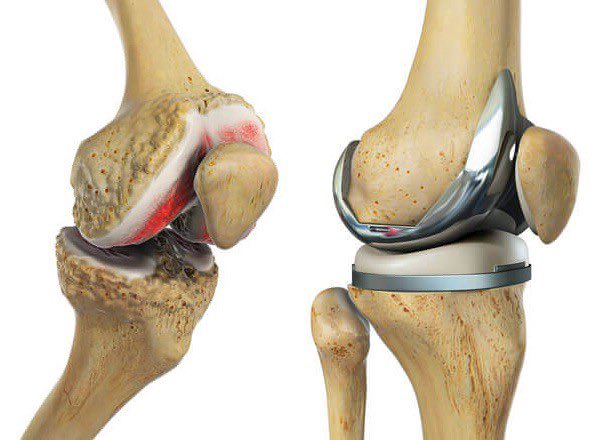

يكون الخيار الجراحي جداً مناسب

حيث يكون مبدئها استبدال او تلبيس مفصل الركبة بمفصل صناعي

حيث تكون نتائجها مرضية و ممتازة اذا أجريت للمريض المناسب